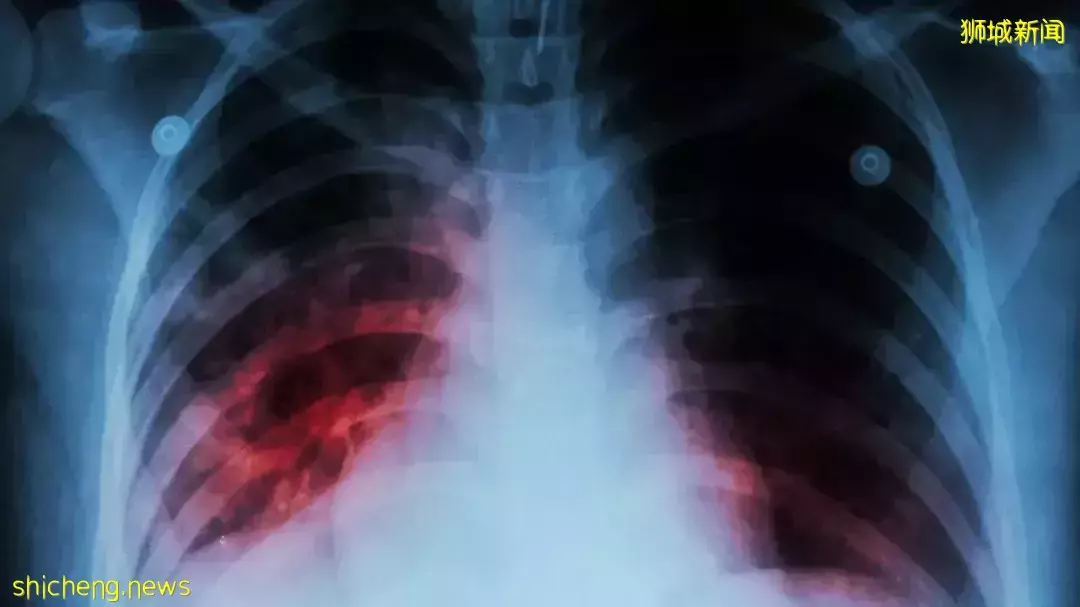

新加坡的組屋竟然突然出現不明肺結核感染群!

目前已有7人出現肺結核,但病例彼此之間沒有接觸!也不曾在同一個地點聚集!

2022年3月2日,衛生部接到7起肺結核病例通報,皆來自惹蘭紅山第2座組屋。

這些患者的確診時間集中在2月到3月期間,且都是同一座組屋的不同住戶。

衛生部經過基因分析後,4月才確認這7起病例由相似基因組成。這意味著肺結核病例之間理應有關聯。

7個病例之間,彼此沒有接觸過,也沒有在同一地點聚集過。可他們卻不約而同確診肺結核。

肺結核的症狀包括持續三周或更長時間的咳嗽、低燒、盜汗、疲勞、體重減輕和胸痛。